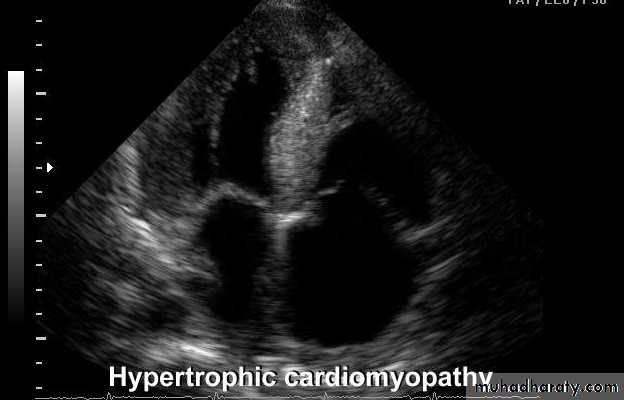

• Hypertrophic cardiomyopathy

ECHO Echocardiography is diagnostic

The hypertrophy may be generalised or confined largely to the interventricular septum (asymmetric septal hypertrophy or other regions (e.g. apical hypertrophic cardiomyopathy)

Dynamic LV outflow tract obstruction ( atleast >30 mm, usually > 50mm Hg)Diastolic dysfunction